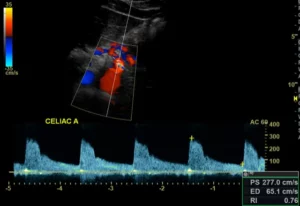

Chronic mesenteric ischemia

Celiac artery stenosis seen on color flow duplex ultrasonography

Duplex, on the other hand, has the advantages of portability, lack of radiation and no need for contrast. Duplex criteria for mesenteric artery stenosis are flow-velocity related. Therefore factors that affect flow velocity such as food and thyroid function should be controlled. Ideally the exam is performed after an overnight fast. Limitations of duplex ultrasonography for imaging the mesenteric blood vessels include inability to visualize beyond gas, poor imaging in obese persons and difficulty interpreting acoustic shadows generated by vessel calcifications. It also can not visualize the inferior mesenteric artery in many cases.